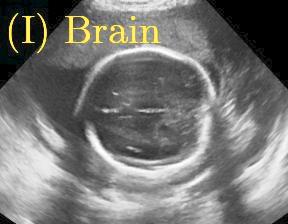

Row I in Fig. 6 shows a fetal brain image from . The confidence estimation of shadow regions from the baseline, the proposed method and the proposedAG method are similarly accurate since we use fetal brain images to train the confidence estimation networks in these three methods. These outperform [16] and [22]. Rows (II-IV) in Fig. 6 show shadow confidence maps of non-brain anatomy from , including lips, abdominal and cardiac. The baseline failed on unseen data during inference. However, the proposed methods are able to generate accurate shadow confidence maps because of the generalized shadow features obtained by the shadow-seg module. Furthermore, the “Lips” example shows that our method is capable of detecting weaker shadow regions that have not been annotated in manual segmentation. This indicates that the confidence estimation network has learned general properties of shadow regions.

We propose a novel method based on convolutional neural networks (CNNs) to automatically estimate pixel-wise confidence maps of acoustic shadows in 2D US images. Our method learns an initial latent space of shadow regions from images consisting of multiple anatomies and with global image-level labels (“has shadow” and “shadow-free”), e.g. Fig. 1(a). The basic latent space is then estimated by learning from fewer images of a single anatomy (fetal brain) with coarse pixel-wise shadow annotations (approximately of the images with global image-level labels), e.g. Fig. 1(b). The resulting latent space is then refined by learning shadow intensity distributions using fetal brain images so that the latent space is suitable for confidence estimation of shadow regions. By using shadow intensity information, our method can detect more shadow regions than the coarse manual segmentation, especially relatively weak shadow regions.